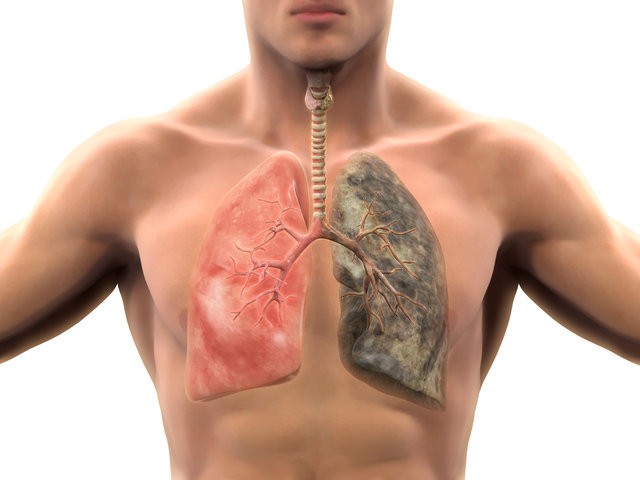

Dünyada hayati tehlikeye en fazla neden olan kanser türü olarak bilinen akciğer kanseri, vücutta meydana gelen küçük değişikliklerin önemsenmesiyle erken dönemde teşhis edilebiliyor. Belirtileri tanımak ve akciğer kanserinin en önemli nedeni olan sigaradan uzak durmak, hastalıkla mücadelede çok büyük bir rol oynuyor.

Erkeklerde en sık görülen kanser türü olan akciğer kanseri, kanserden ölüm nedenleri arasında birinci sırada yer alıyor.